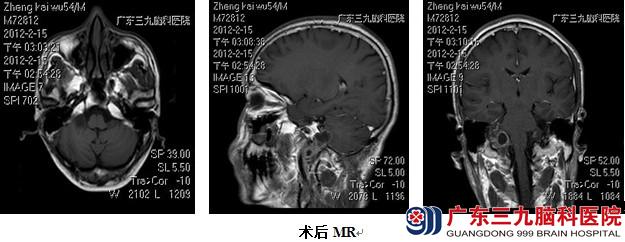

检查结果显示,该肿瘤约3.3×2.9×3.7cm。完善术前准备后,在全麻下行右侧乙状窦后枕下入路颈静脉孔区肿瘤切除术,术中见右侧颈静脉孔区粉白色肿物,包膜完整,血供较丰富,打开蛛网膜及肿瘤包膜,先进行瘤内分块切除,然后游离切除瘤壁,最终达到全切肿瘤。